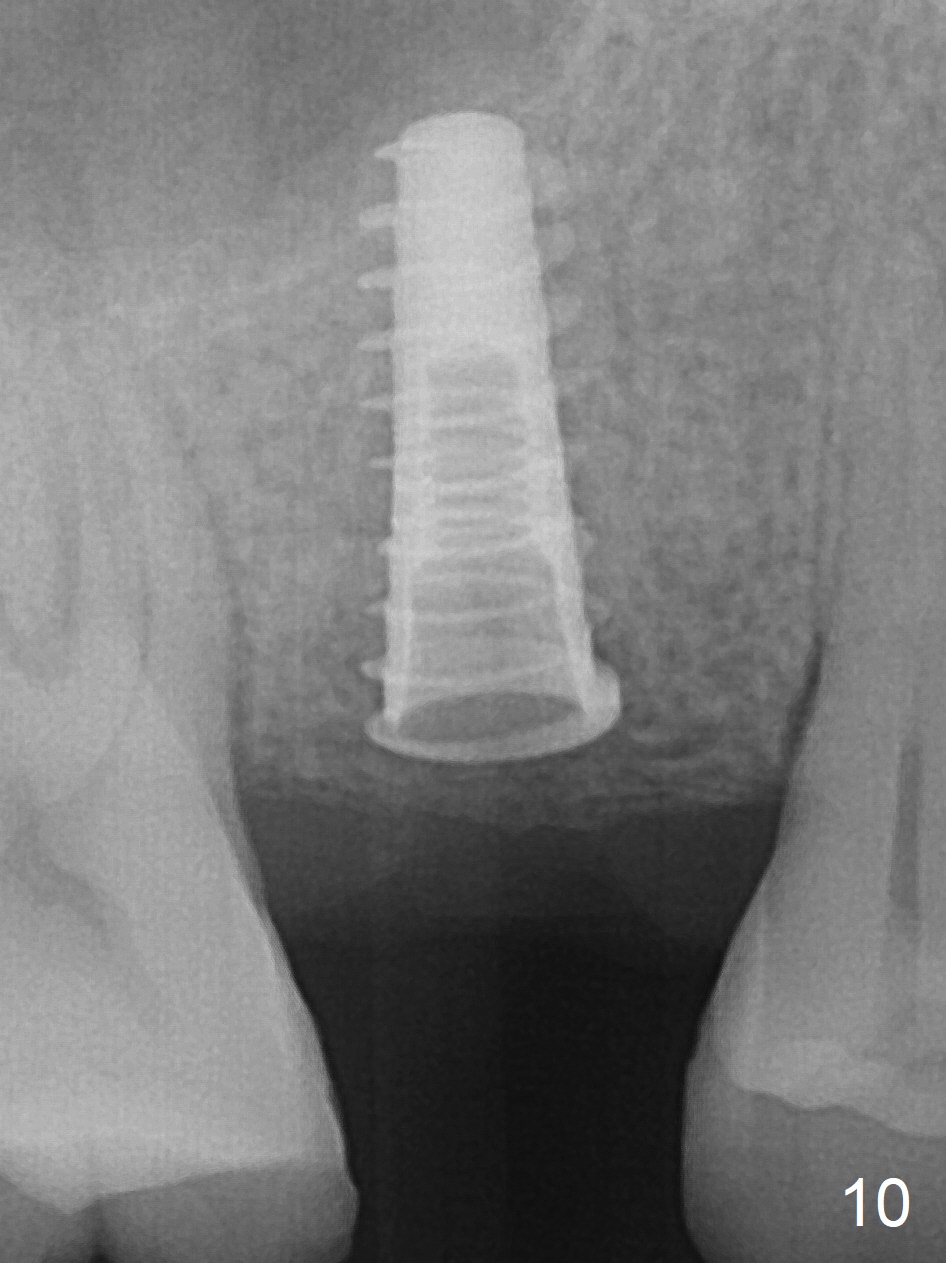

A 47-year-old man returns emergently with subgingival fracture of the lingual (L) cusp of the tooth #4 (Fig.1-3).  After extraction (no bony defect) without drilling, a 4x11 mm dummy implant is placed as a tap drill with satisfactory stability (Fig.4,5).  To get subcrestal placement, a shorter (4x9 mm) implant is inserted with insertion torque of < 35 Ncm.  In retrospect, a larger implant (4.5 mm) would be better in term of primary stability.  After allograft placement into the buccal and lingual gaps, a 4.5x4(4) mm abutment is placed for an immediate provisional.  There is a peri-implant gap 7 months postop (Fig.7<, as compared to the implant at #2 (6 months postop)) .  When the loose abutment is being retightened, the patient feels pain, although the gingiva appears healthy (Fig.8).  A larger implant should have been used; the abutment should have been removed.  The implant dislodges while the abutment is untightened 8 months postop.  The osteotomy is found intact.  A 4.5x11 mm dummy implant is placed 2 mm subgingival with 20 Ncm (Fig.9).  When a 4.5x11 mm definitive implant is placed 3 mm subgingival (Fig.10,11), torque reaches 50 Ncm.  A 5.5x3 mm healing abutment is placed.  Three months postop, the implant is stable (Fig.12,13) and impression is taken.